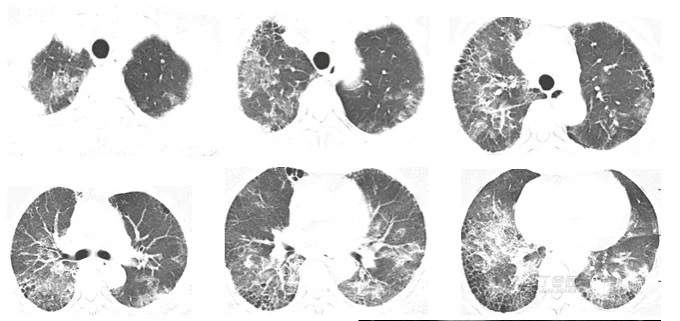

2023年1月9日因喘息于某市医院,给予甲泼尼龙40mg qd五日,患者自感无明显好转;2023年1月26日再次因喘息、呼吸困难加重于某市医院就诊,行冠脉造影示:左前降支狭窄30%,左回旋支近段狭窄50%,胸部CT:双肺磨玻璃影,双肺间质纤维化。心脏彩超:重度肺动脉高压(69mmHg)。考虑“冠心病、肺部感染、肺间质纤维化、重度肺动脉高压”,予冠心病二级预防等治疗,但呼吸困难无明显好转;

CTA(2023-2-8): 1. 双肺见散在斑片状、片状、条索状密度增高影,双肺胸膜下及双肺下叶肺组织呈网格状改变,考虑肺间质纤维化并炎症;2.左上、下肺动脉起始处可见少许条形充盈缺损影。

胸部CT复查(2023-2-16):双肺见散在斑片状、片状、条索状密度增高影,双肺胸膜下及双肺下叶肺组织呈网格状改变,多考虑肺间质纤维化并炎症,对比前片局部斑片影较前稍减少。